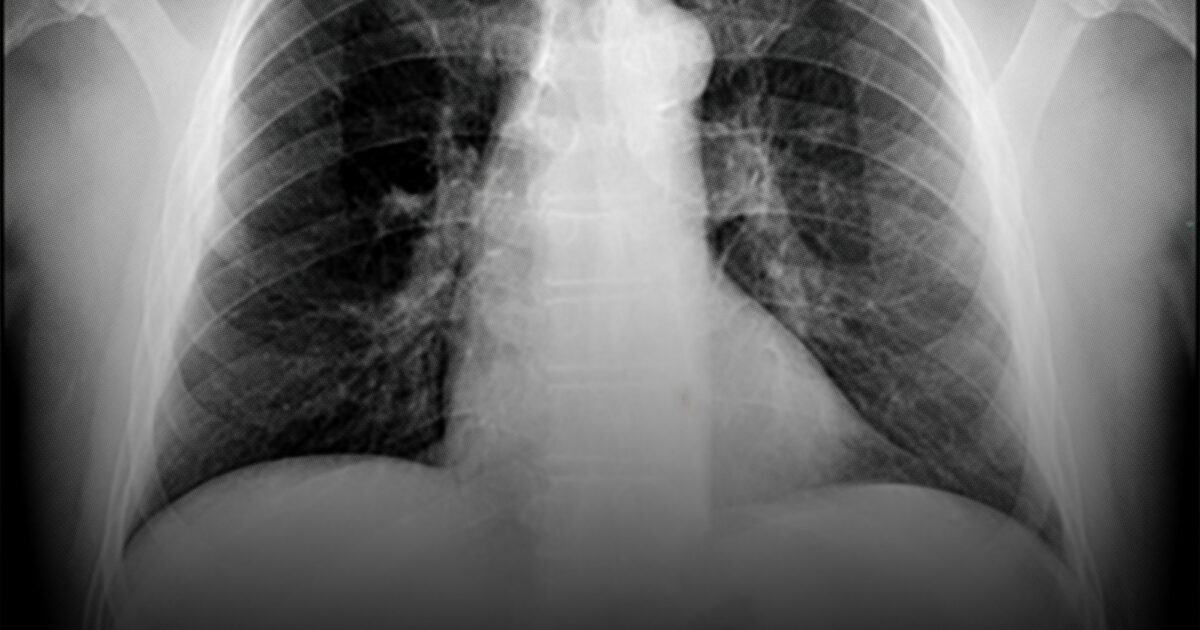

The engineered stone industry is worth nearly $30 billion. But the workers at its core are falling sick and dying from an illness called silicosis. Now these wo...